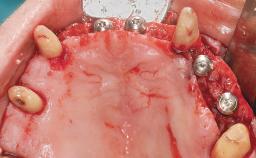

Conventional Loading of Eight Implants in the Maxilla and Final Restoration with a Full-Arch Gold-Ceramic FDP

A 35-year-old Caucasian female presenting with advanced periodontal disease involving both the maxillary and the mandibular dentition was referred for evaluation. The patient, a non-smoker in good general health, requested treatment for recurrent periodontal abscesses, tooth mobility, and discomfort during chewing, as well as restoration of her missing teeth with a fixed prosthesis to improve mastication and esthetics. All residual maxillary teeth exhibited plaque deposits, deep pockets, bleeding on probing, and class III mobility and were evaluated as hopeless. All residual mandibular teeth except tooth 37 could be maintained after periodontal therapy.

# of Implants 8

Bone Augmentation Horizontal|Staged|Vertical

Augmentation Materials Autogenous block(s)

Defining Characteristics Fully edentulous upper jaw to be rehabilitated with four or more implants